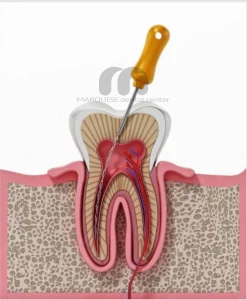

عصب کشی دندان

عصبکشی دندان؛ راهنمای کامل برای حفظ سلامت دندانها عصبکشی دندان چیست؟ عصبکشی یا Root Canal Treatment یکی از درمانهای دقیق دندانپزشکی است که به نجات دندانهای عفونی یا آسیبدیده کمک میکند. زمانی که بافت زندهی داخل دندان (پالپ) به دلیل پوسیدگی یا ضربه دچار التهاب میشود، این درمان میتواند درد را از بین ببرد و دندان را حفظ کند. در کلینیک دندانپزشکی مارکیز، دندانپزشکان مجرب با استفاده از تجهیزات مدرن و مواد باکیفیت، عصبکشی را با دقت بالا انجام میدهند تا سلامت و زیبایی دندان حفظ شود. چه زمانی نیاز به عصبکشی دندان دارید؟ درد شدید یا مداوم، اولین نشانهی نیاز به درمان ریشه است. همچنین اگر دندانتان به سرما یا گرما حساسیت طولانی دارد، لثه اطراف آن متورم شده

هزینه عصب کشی و پر کردن دندان در سال 1405 | تعرفه واقعی در تهران 💎 هزینه عصب کشی و پر کردن دندان در سال 1405 چقدر است؟ دندان درد یکی از مشکلاتی است که معمولاً نیاز به درمان فوری دارد. در بسیاری از موارد، زمانی که پوسیدگی به عصب دندان میرسد، انجام عصب کشی و سپس ترمیم یا پر کردن دندان ضروری میشود. یکی از سوالات رایج بیماران این است که هزینه عصب کشی و پر کردن دندان در سال 1405 چقدر است و چه عواملی روی قیمت نهایی تأثیر میگذارند؟ در کلینیک دندانپزشکی مارکیز در پونک تهران، خدمات عصب کشی و ترمیم دندان با استفاده از تجهیزات دیجیتال، بیحسی بدون درد، مواد باکیفیت و در محیطی VIP انجام

هزینه عصبکشی دندان در سال ۱۴۰۴ در تهران 💎 هزینه عصبکشی دندان در سال ۱۴۰۴ برای بسیاری از بیماران به یکی از دغدغههای مهم تبدیل شده است. عصبکشی یا درمان ریشه زمانی انجام میشود که عفونت یا آسیب به پالپ دندان برسد و اگر بهموقع درمان نشود، ممکن است منجر به کشیدن دندان شود. در کلینیک دندانپزشکی مارکیز در پونک تهران، خدمات تخصصی عصبکشی دندان با استفاده از تجهیزات مدرن برای ساکنین سعادتآباد، شهرک غرب، مرزداران، زعفرانیه، ولنجک، فرشته و فرمانیه ارائه میشود 💎 عصبکشی دندان چیست و چه زمانی لازم است؟ عصبکشی دندان روشی درمانی برای حذف بافت عفونی داخل ریشه دندان و جلوگیری از گسترش عفونت است. این درمان معمولاً در موارد زیر انجام میشود: پوسیدگی عمیق دندان